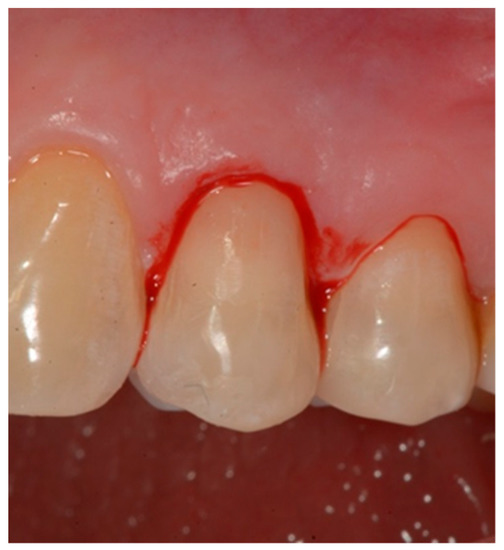

- Isolation of the field with a retraction cord 000 in the gingival sulcus (Ultrapak; Ultradent, 505 West Ultradent Drive South Jordan, UT, USA) (Figure 3).